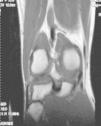

Figura 5 RM. Imagen potenciada en T1. Cuerpos libres alrededor de los ligamentos cruzados y en otras localizaciones intraarticulares.

Figura 6 Artroscopia. Cuerpos libres alrededor de los ligamentos cruzados y en otras localizaciones intraarticulares.

Figura 7 Artroscopia. Cuerpos libres alrededor del ligamento cruzado íntegro.

Figura 8 Artroscopia. Cuerpos libres alrededor del ligamento cruzado íntegro.